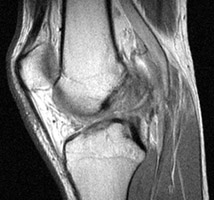

Sagittal T2 weighted and proton density images which reveal complete tear of the ACL with mild increase in marrow signal in the adjacent osseous structures. The bone bruises, as evidenced by increased signal within the marrow, is likely caused by anterior subluxation of the tibia at the time of tear of the ACL accompanied by impaction of the middle portion of the lateral femoral condyle against the posterior portion of the lateral tibial plateau. Signal intensity abnormalities are probably secondary to edema, hemorrhage, and microfracture.

T2W - Click on the image for a larger versionAProton Density - Click on the image for a larger versionB